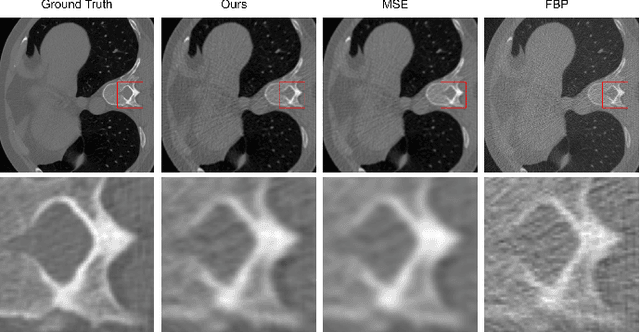

Abstract:Computed Tomography (CT) image reconstruction is crucial for accurate diagnosis and deep learning approaches have demonstrated significant potential in improving reconstruction quality. However, the choice of loss function profoundly affects the reconstructed images. Traditional mean squared error loss often produces blurry images lacking fine details, while alternatives designed to improve may introduce structural artifacts or other undesirable effects. To address these limitations, we propose Eagle-Loss, a novel loss function designed to enhance the visual quality of CT image reconstructions. Eagle-Loss applies spectral analysis of localized features within gradient changes to enhance sharpness and well-defined edges. We evaluated Eagle-Loss on two public datasets across low-dose CT reconstruction and CT field-of-view extension tasks. Our results show that Eagle-Loss consistently improves the visual quality of reconstructed images, surpassing state-of-the-art methods across various network architectures. Code and data are available at \url{https://github.com/sypsyp97/Eagle_Loss}.